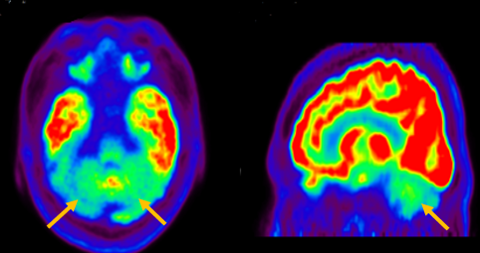

진행 핵상 마비는 대표적인 파킨슨 증후군 중의 하나입니다. 파킨슨병과 다른 점은 질병의 초기부터 중심을 잡기 어려운 체위 불안정이 나타나 자주 넘어진다는 것입니다. 파킨슨병의 경우 질병이 상당히 진행된 뒤에 체위 불안정이 나타납니다. 또한 진행 핵상 마비에서는 목 주위 근육을 비롯한 몸 중심 근육의 경축이 나타나, 목을 뒤로 젖히면서 걷는 모습이 보입니다. 그리고 눈의 운동을 조절하는 기능에 장애가 나타나 아래쪽을 바라보는 데 문제가 생겨 계단을 내려갈 때 어려움을 겪는 경우가 많습니다. 진행 핵상 마비가 의심되는 경우, 뇌 자기공명영상(MRI)에서 중뇌의 위축이 비정상적으로 심하게 나타나는 소견을 확인하거나, 뇌포도당 양전자 단층촬영(PET)에서 전두엽과 중뇌의 대사 기능이 저하된 소견을 확인하여 진단에 참고할 수 있습니다.

[진행핵상마비 환자의 뇌포도당 양전자 단층 촬영에서 확인되는 중뇌의 대사 저하 소견]

다계통 위축이란 뇌의 다양한 계통에서 위축이 발생하는 것을 의미합니다. 파킨슨 증상이 있으면서 질병 초기에 소변 장애나 기립성 저혈압으로 인한 어지러움이 두드러지게 나타나는 경우, 보행 시 비틀거림이나 구음 장애와 같은 소뇌 위축에 따른 운동 실조 증상이 나타나는 경우, 꿈에서 하는 행동을 수면 중에 보이는 렘수면 행동 장애가 동반되는 경우 다계통 위축을 의심합니다. 다계통 위축은 파킨슨병과 달리 안정 시 떨림이 잘 보이지 않고, 증상이 대칭적인 경우가 많으며, 진행이 빠르며, 레보도파와 같은 항파킨슨 약제에 잘 반응하지 않습니다. 다계통 위축은 뇌 자기공명영상(MRI)에서 교뇌에 십자 모양의 고음영이 나타날 수 있는데, 이를 십자무늬 빵(hot cross bun) 징후라고 합니다. 또한 초기에서는 뇌 자기공명영상(MRI)이 정상으로 보이더라도 뇌포도당 양전자 단층촬영(PET)에서는 소뇌 또는 기저핵의 대사 기능이 저하된 상태가 관찰될 수 있습니다. 이러한 영상 소견은 특징적인 임상 증상과 함께 진단에 참고할 수 있습니다.

[다계통위축 환자의 뇌포도당 양전자 단층 촬영에서 확인되는 소뇌의 대사 기능 저하]